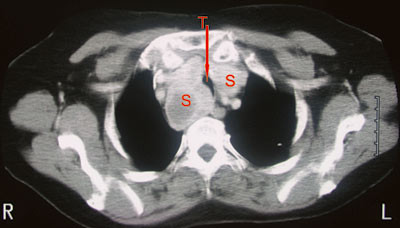

Ved undersøkelse virket pasienten eutyreot, hadde ikke takypné, men inspiratorisk stridor. Strumaet var betydelig, beveget seg litt ved svelging og var forholdsvis mykt og uømfintlig. CT av halsen og mediastinum viste betydelig cervikalt og intratorakalt struma med tracheadeviasjon og betydelig lumenkompresjon (fig 2).

Bildeundersøkelser og cytologi

Røntgen trachea, røntgen thorax eller bedre CT thorax (fig 2, fig 3) eller MR-undersøkelse kan avdekke og kvantitere intratorakalt struma, tracheadeviasjon eller -kompresjon. MR er mest nøyaktig, men også mest ressurskrevende. Med MR unngår man å gi jodholdig kontrast som kan gi kontrastmiddelindusert hypertyreose ved preeksisterende jodmangel og forstyrre videre nukleærmedisinsk diagnostikk og terapi i flere uker til måneder (17). Konvensjonell røntgen, CT eller MR er ikke indisert ved ukomplisert, lite struma eller ved knuter i en ellers upåfallende thyreoidea.